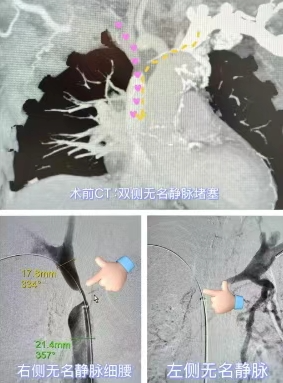

结合姚女士的病史和详细的血管影像学检查,CT提示双侧无名静脉重度狭窄几乎闭塞,诊断:上腔静脉综合征,这正是导致姚女士右上肢肿胀、静脉回流障碍的“罪魁祸首”。此类疾病往往病情凶险,传统手术风险极高。

多入路建立,全面开通通路。医生精准穿刺双上肢浅静脉和双侧股静脉置管,建立了关键的微创操作通道。这一多入路策略为后续多角度开通严重狭窄/闭塞的上腔静脉提供了至关重要的操作路径和支撑。

明确诊断,导丝穿越难关。造影清晰揭示了上腔静脉存在严重的狭窄/闭塞。医生凭借精湛的技艺,巧妙运用导丝技术,通过多入路协同努力,艰难地成功穿越了闭塞段,为后续治疗建立了生命线。